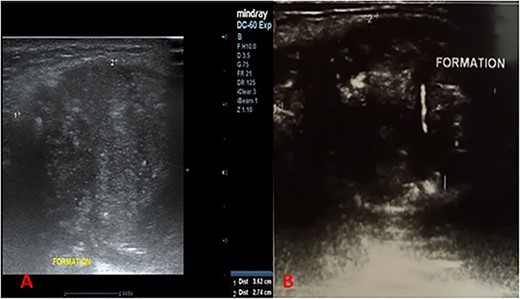

This was a 44-year-old female patient, with no specific pathological history, who consulted for a painless, median, anterior cervical swelling that had been progressively evolving for 2 and a half years. There was no evidence of dysphonia, dysphagia or cough. Physical examination revealed a median tumefaction, in contact with the sub-hyoid bone, oval in shape with a transverse major axis of about 6 cm, rising on swallowing and tongue protraction, painless, firm to palpation, regular in outline, with no inflammatory signs (Fig. 1). We suggested atypical TTC, dermoid cyst or ectopic thyroid nodule as diagnostic hypotheses, and requested further investigations. Cervical ultrasonography revealed a heterogeneous oval formation with internal calcifications, more or less regular contours, posterior reinforcement, relatively thick-walled, anterior cervical location, pushing back the muscles laterally and posteriorly, poorly vascularized on Doppler (Fig. 2A and B). The thyroid gland was normal in size, with a finely nodular echostructure.

Longitudinal cervical ultrasound sections showing a heterogeneous formation, with more or less regular contours, associated with microcalcifications (A) with liquid portions showing posterior enhancement (B).